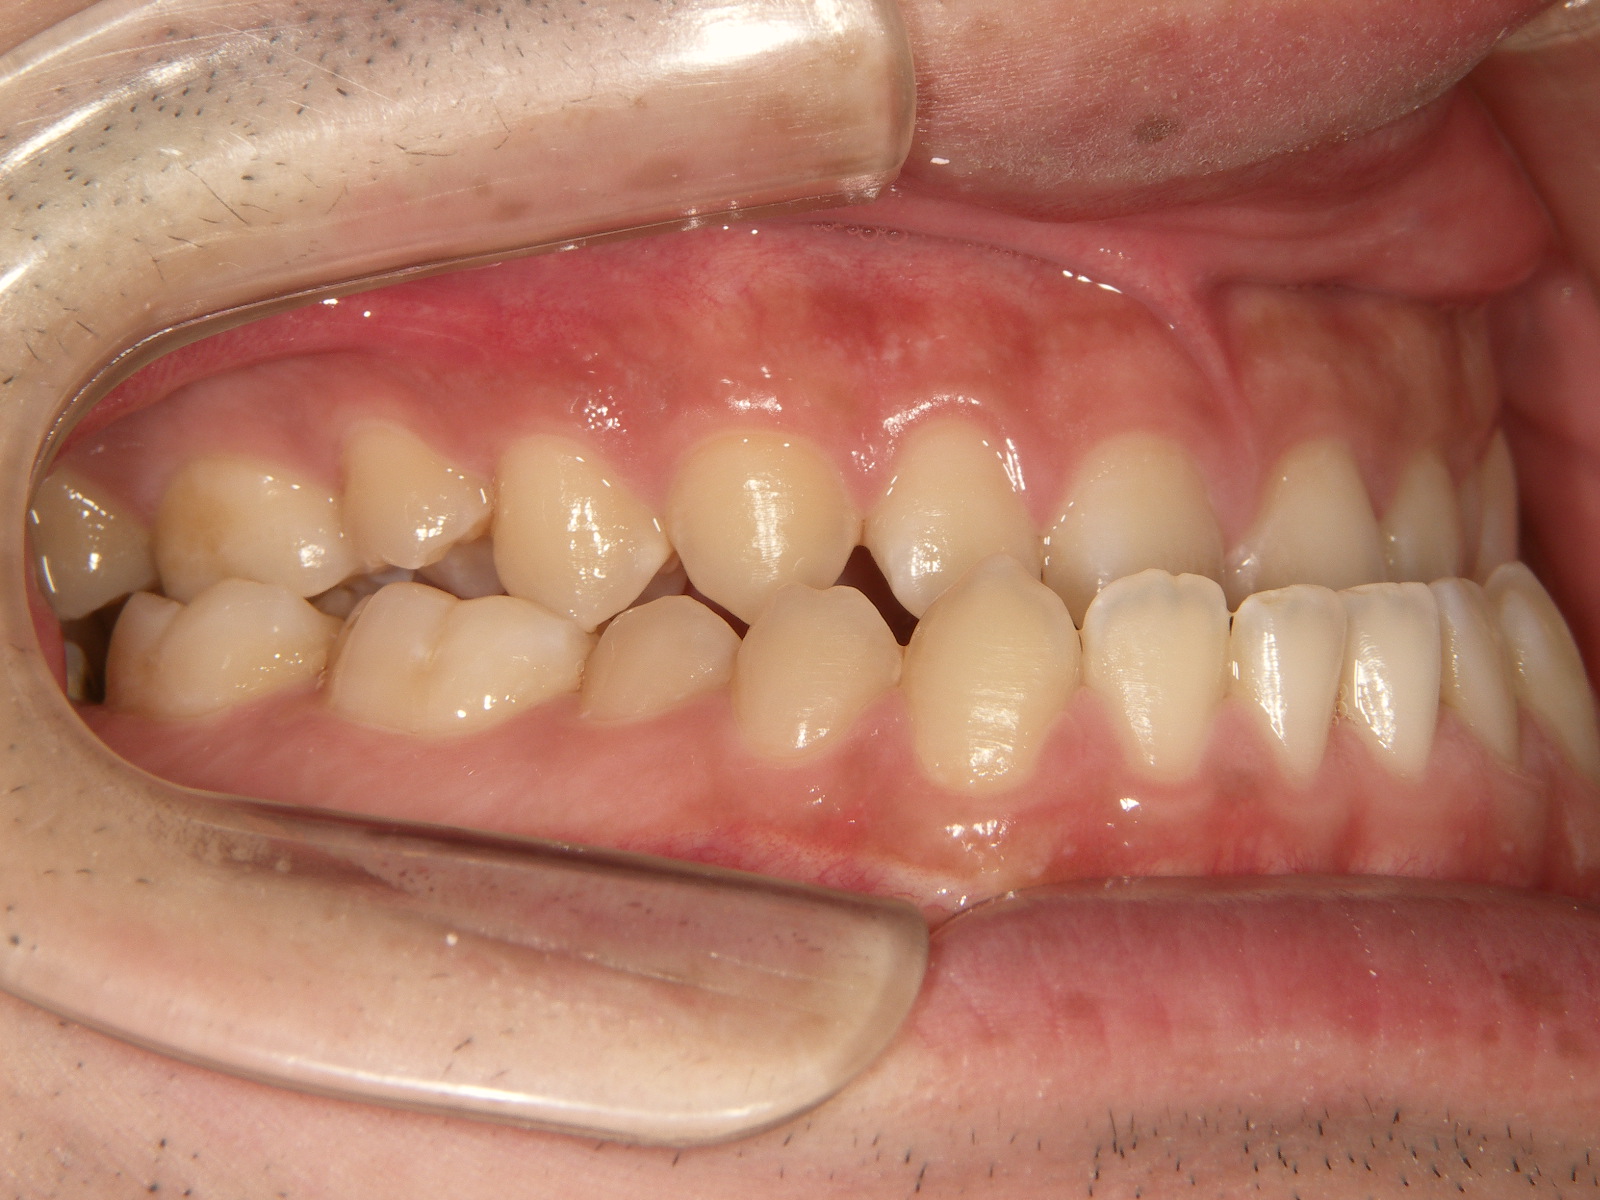

④矯正治療後

矯正装置を外した後の歯並びです。

上下のかみ合わせがしっかりと噛み合い、機能面も歯並びもバランスの良い状態になりました。